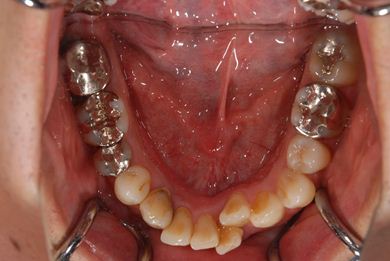

| 性別/年齢 | 男性 / 37歳 | ||||||||||||||||||||||||||||||||

| 主訴 | 数年前に神経を抜く治療をした下顎の歯が、1年ほど前にうずきを感じて治療をした際に、完全に治療するのは難しいと言われた。その歯がぐらつくように感じ始めたので、相談のために来院。 | ||||||||||||||||||||||||||||||||

| 治療内容 | インプラント1本(GBR)、メタルボンドセラミック1本 | ||||||||||||||||||||||||||||||||